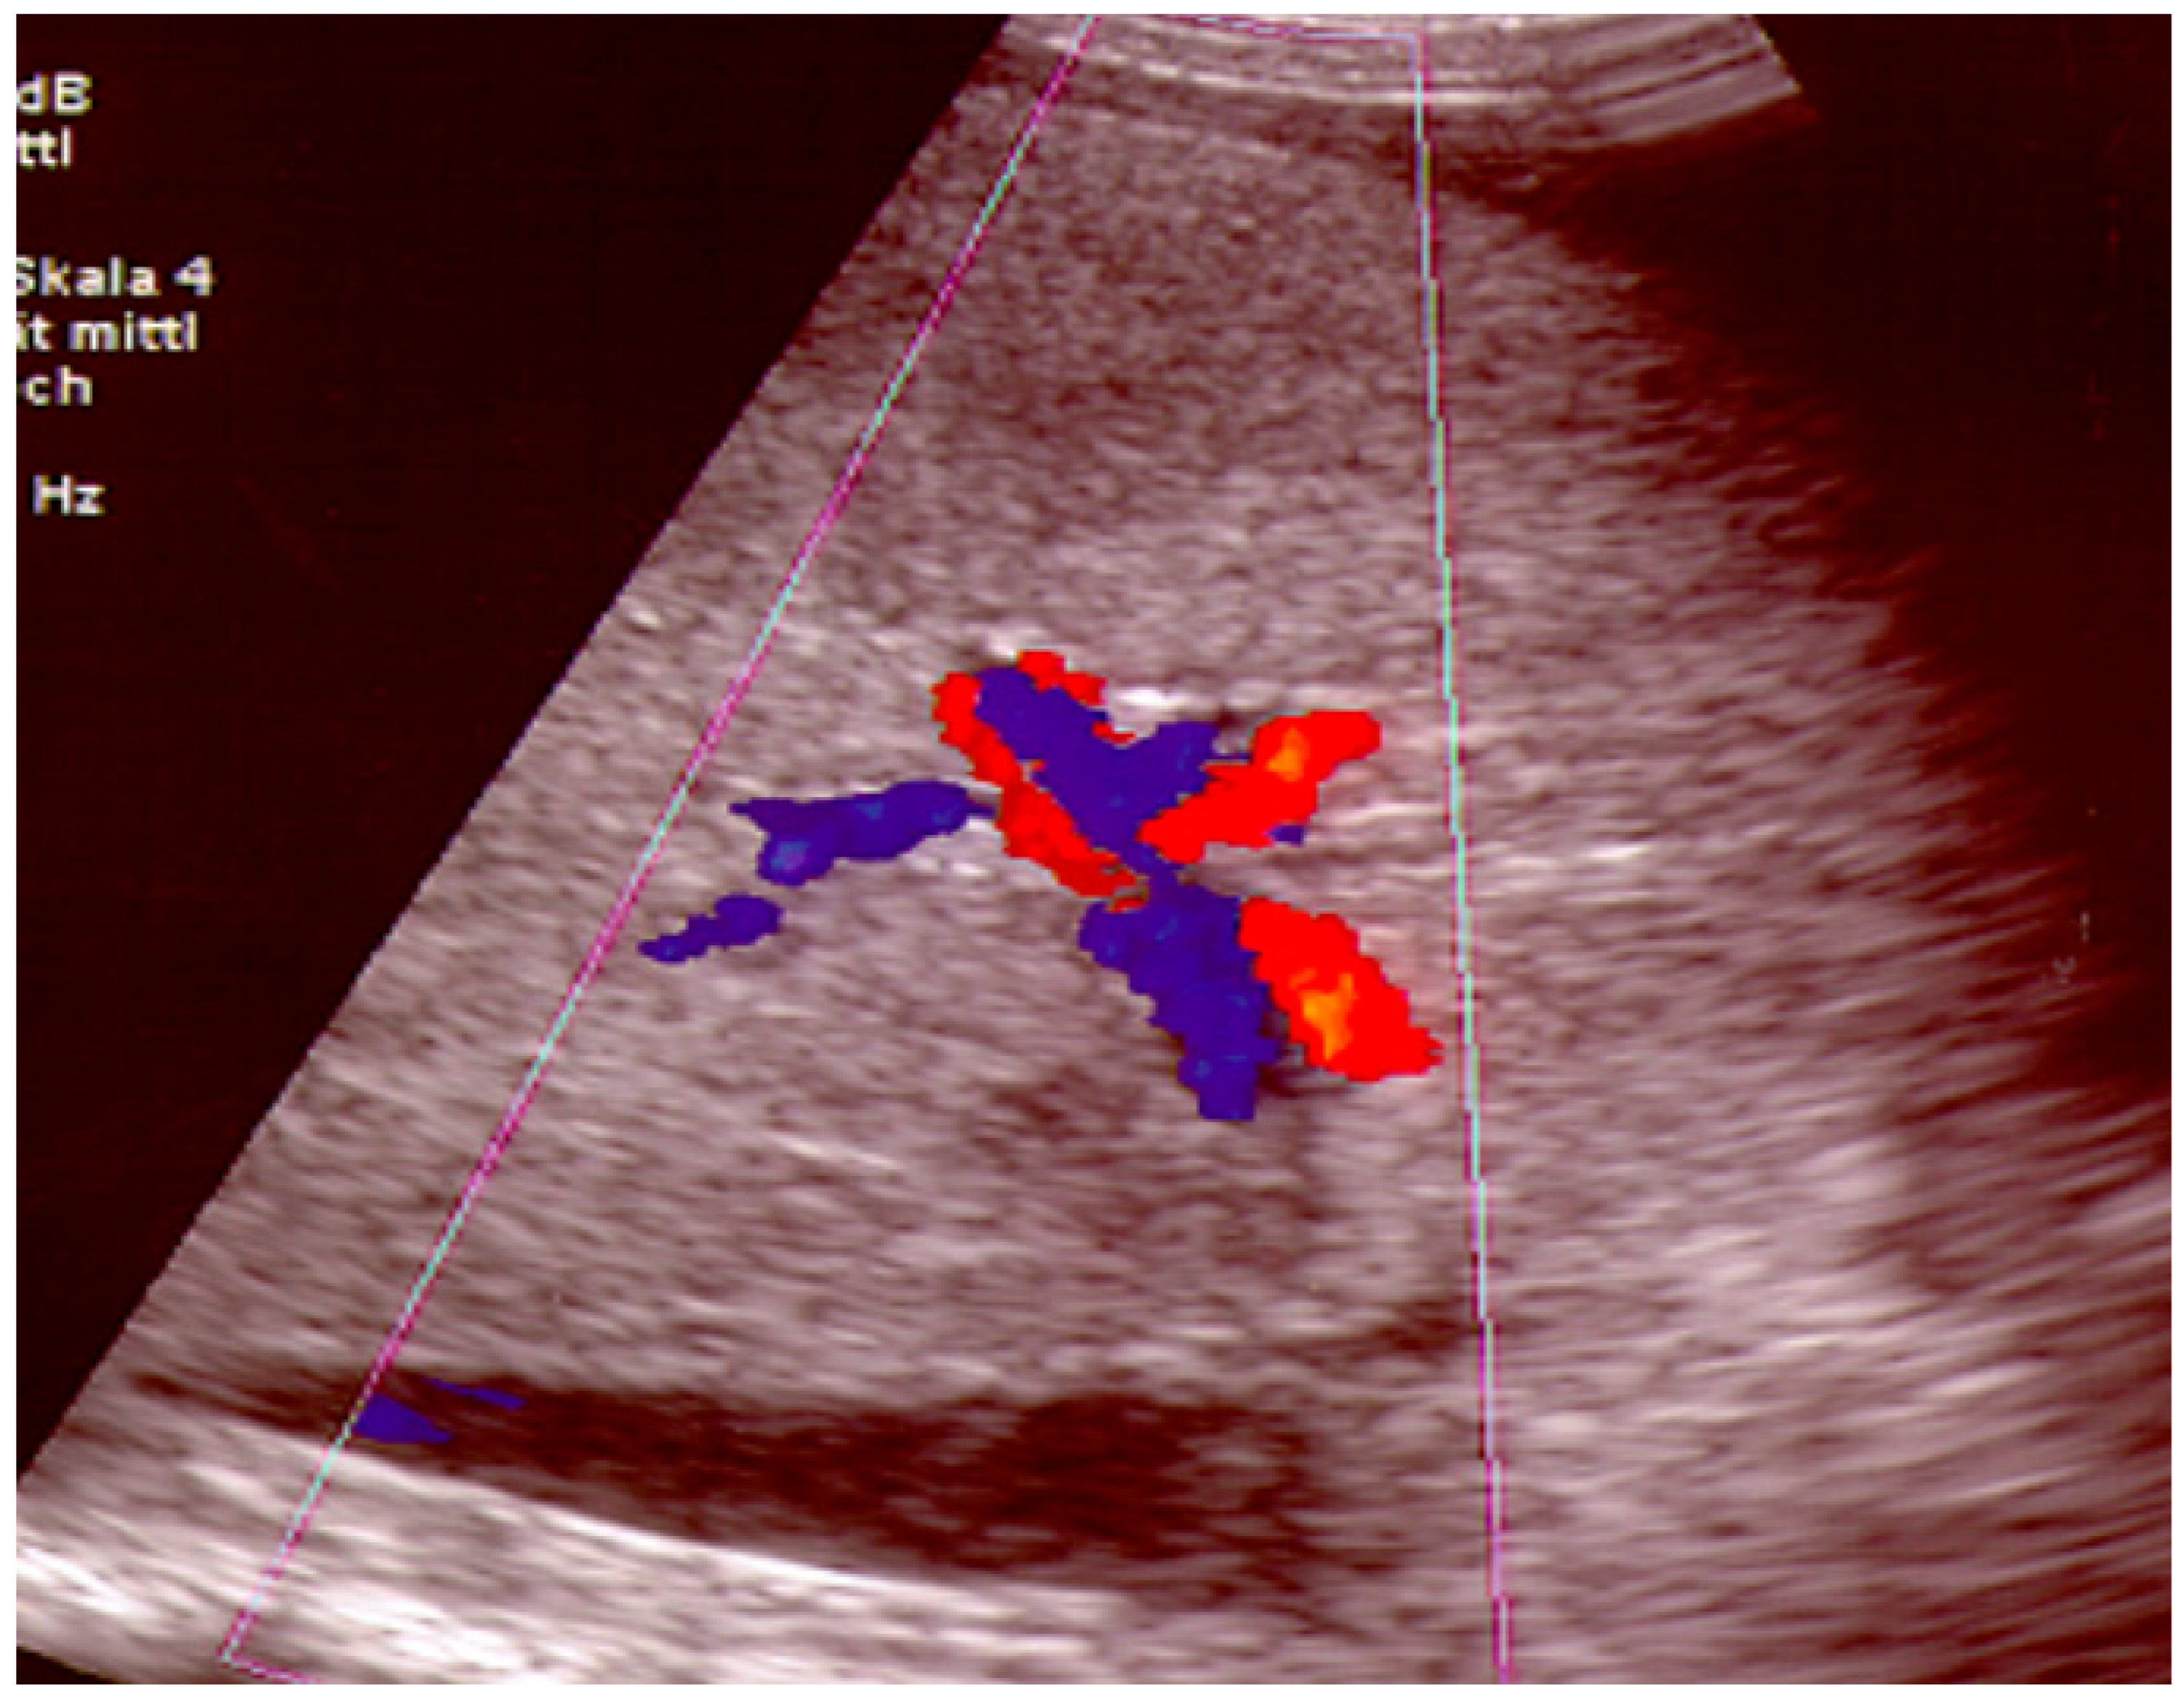

2.1. Angioplasty

2.1.2. Technique